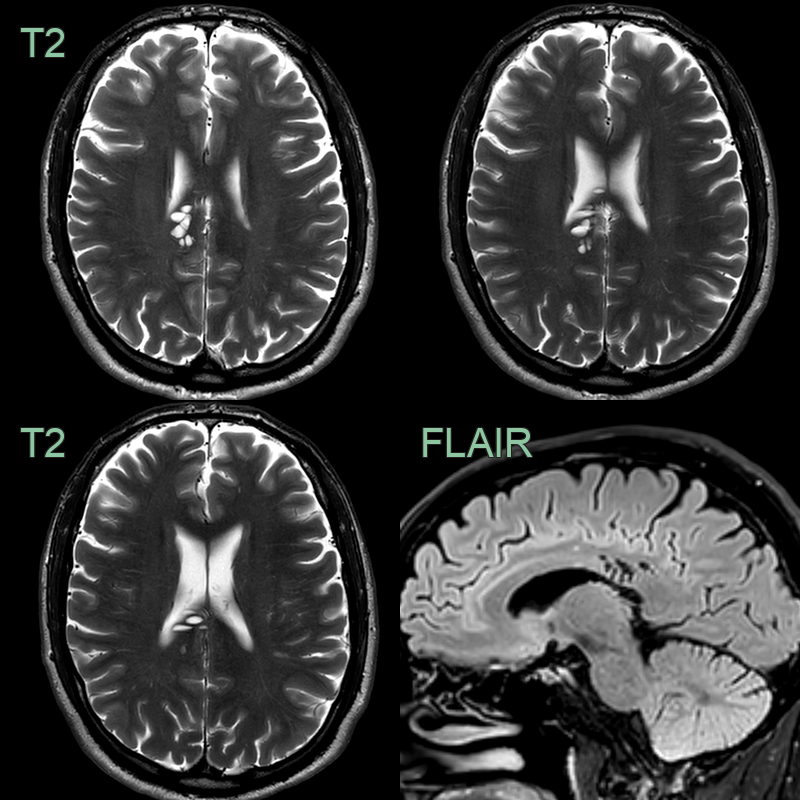

• A cluster of T2-hyperintense lesions centred on the right cingulum fully suppressed on FLAIR and had no surrounding parenchymal signal change.

• There is an enlarged perivascular space (T2-hyperintense and fully suppressing on FLAIR) in a typical location; in the subganglionic region.

• Incidental finding of a clustered subcortical CSF signal without mass effect was consistent with enlarged perivascular spaces.

• With no FLAIR hyperintensity, an MVNT was not likely.